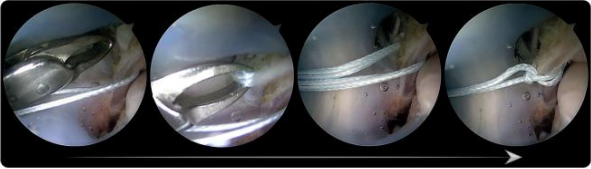

开展关节镜下应用ATiFL的远端束转位加强修复治疗踝关节外侧不稳的修复手术和早期康复诊疗方案。

“每一次操作必须精准到毫米”

张磊说:“这个技术定位病灶准确,切实解决了临床难点。之前1个小时才能完成的手术,现在打两个5mm的小孔,15-20分钟就完成了。”为超重、运动要求高的患者或质量欠佳的ATFL损伤提供一种新的治疗技术。